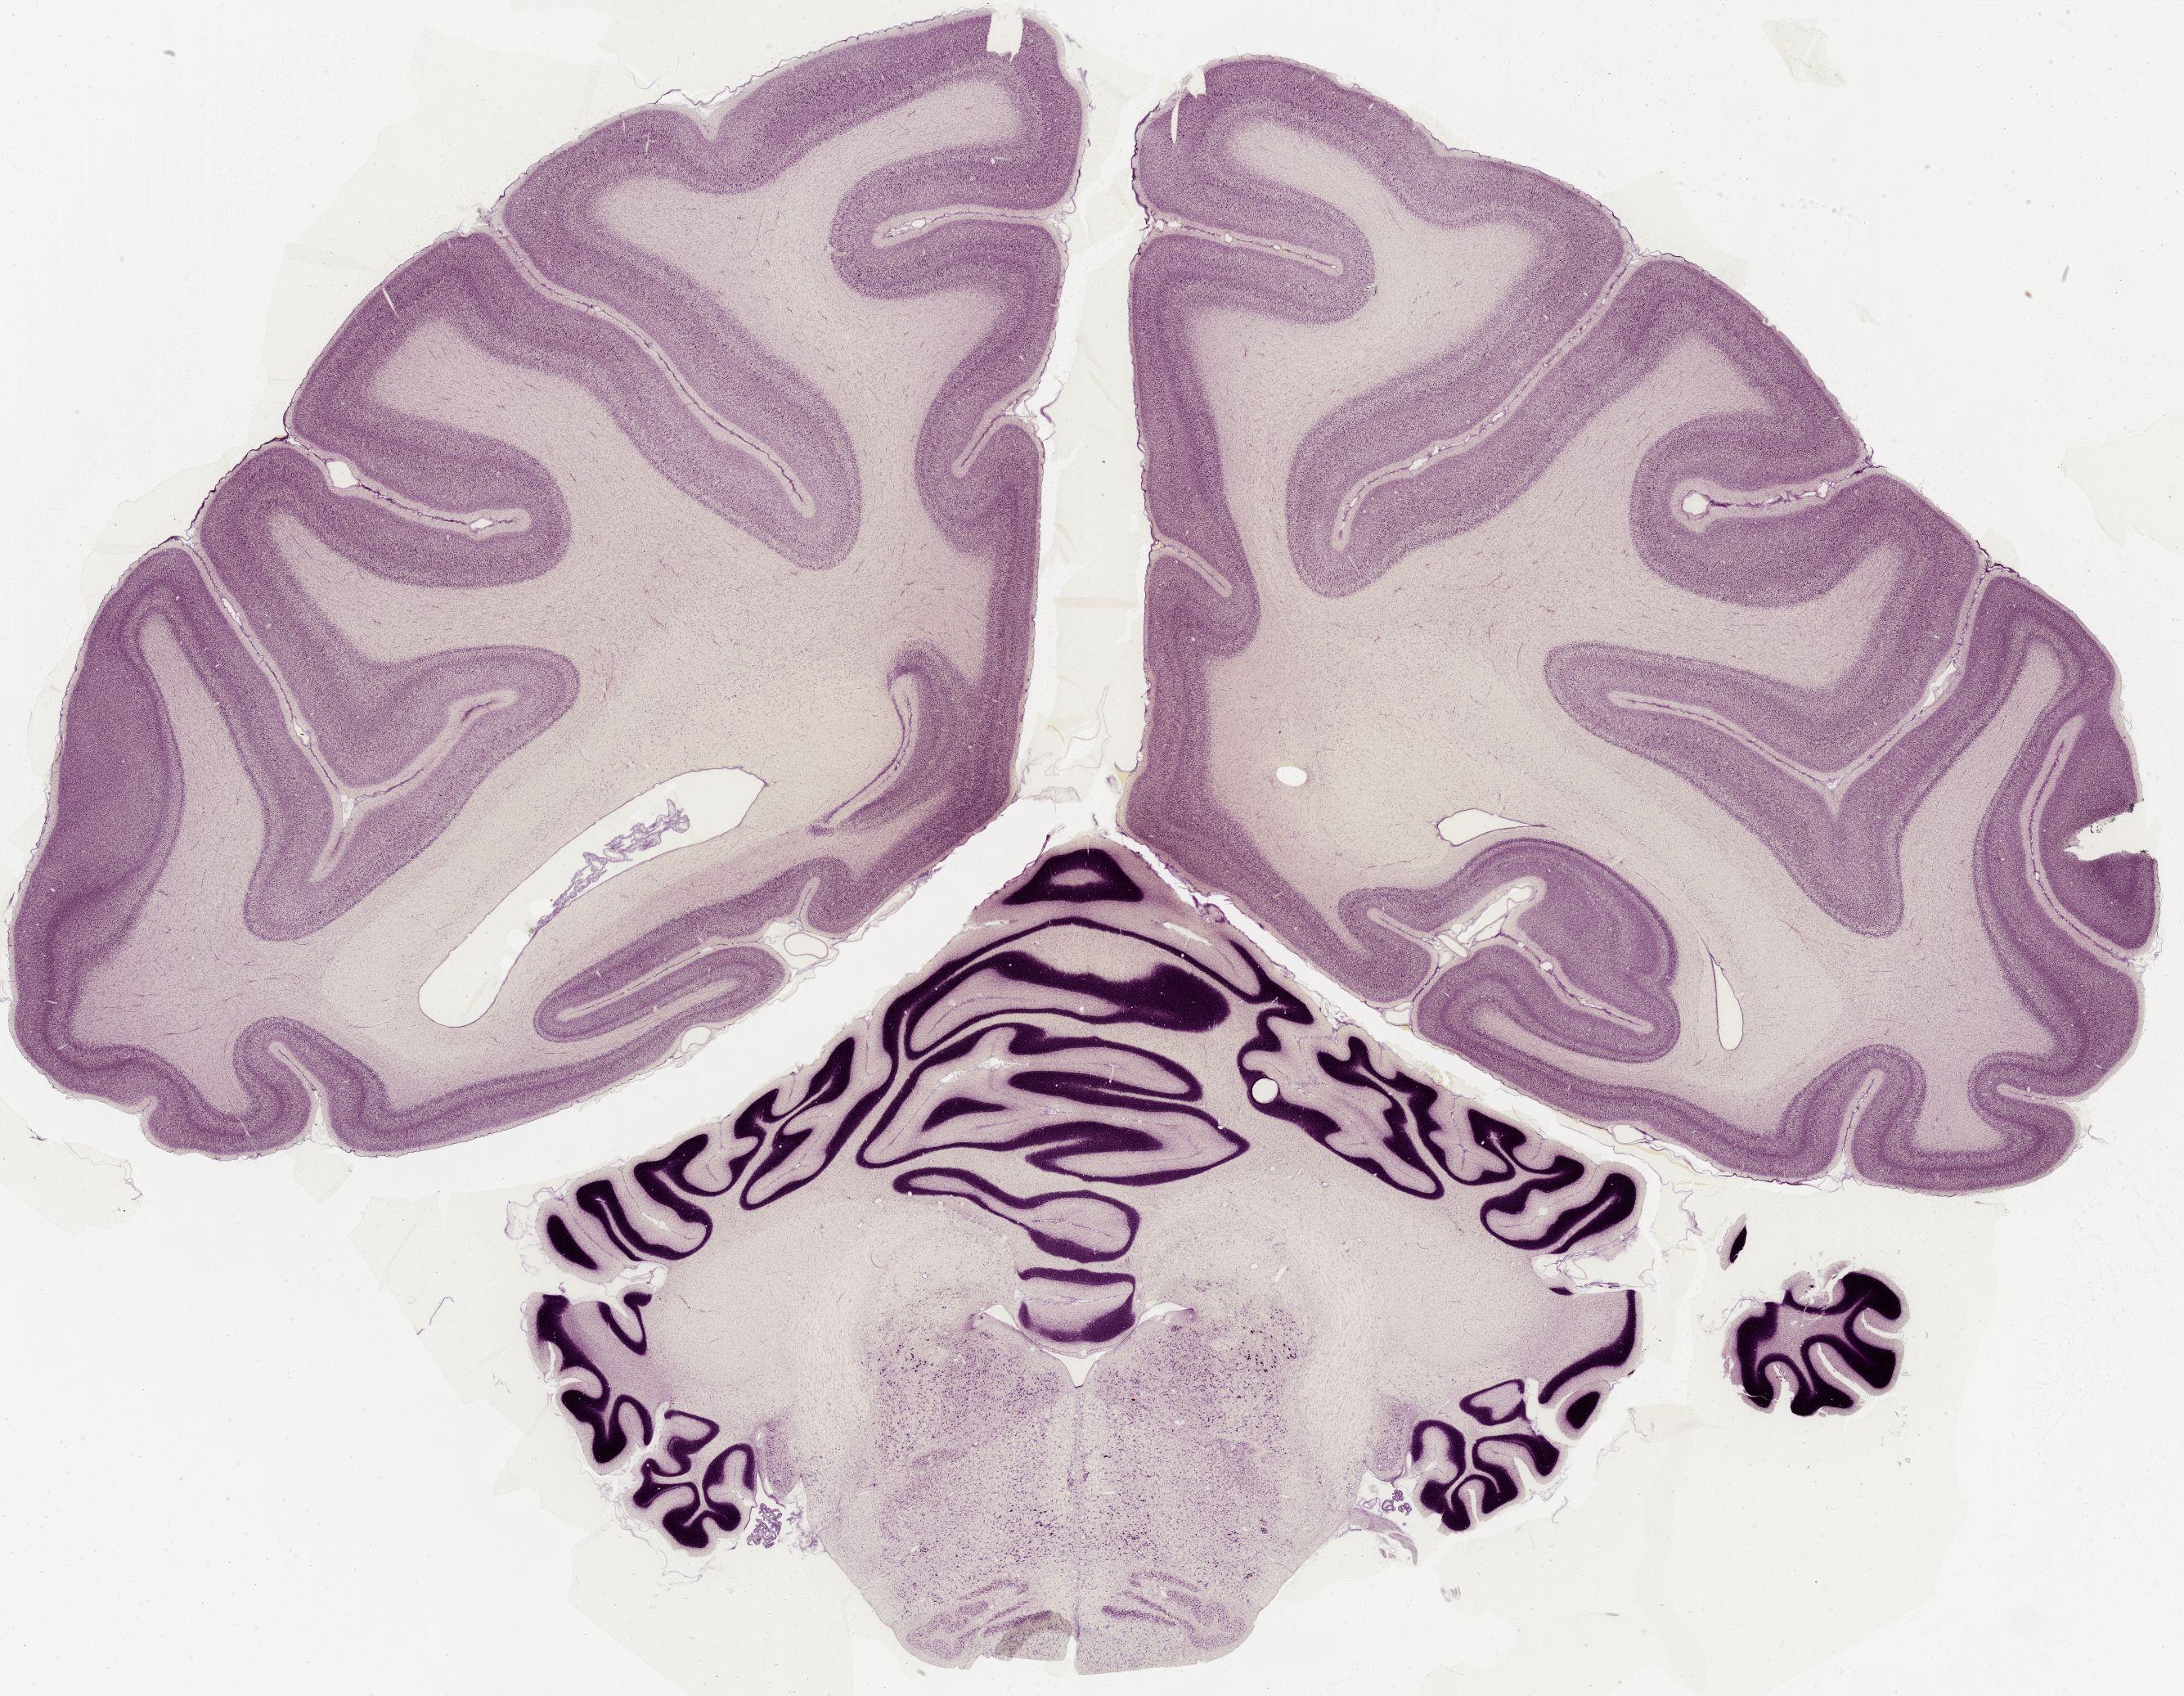

Datasets -> Macaca Mulatta -> Nissl, coronal, histo, Whole-Brain, adult

[ Metadata ]   ·   Source: Edward G. Jones

thumbnail

0650 - labeled